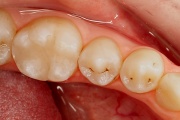

Hambakaaries

kaaries